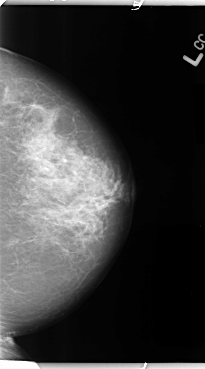

B_3116_1.LEFT_MLO

LEFT_MLO LINES 4672 PIXELS_PER_LINE 2816 BITS_PER_PIXEL 12 RESOLUTION 50 NON_OVERLAY